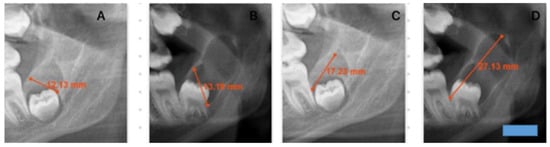

This retrospective study evaluated the radiographic records of patients who presented to the Department of Oral and Maxillofacial Surgery at Dicle University Faculty of Dentistry between 2020 and 2024, underwent biopsy, and received a histopathological diagnosis of dentigerous cysts. Among 187 patients with a definitive post-treatment diagnosis, 12 had previously been scheduled for surgical intervention but failed to attend their appointments (Table 1). Only histopathologically confirmed dentigerous cysts were included in the study. Consequently, radiolucent lesions that could mimic dentigerous cysts were excluded, which inherently limited the scope for comparative analysis. These individuals later returned to the clinic after varying intervals of time. Prior to treatment, new panoramic radiographs were obtained, and repeat biopsies reconfirmed the diagnosis of dentigerous cysts. As patients were informed about the potential risk of neoplastic transformation of these cysts, they were encouraged not to delay treatment, and due to the small number of individuals who postponed their procedures, the sample was limited to 12 patients. To be included in the study, lesions had to remain untreated solely for patient-related reasons, and follow-up panoramic radiographs suitable for comparison had to be available at least six weeks after the initial imaging. In our study, among the included radiographs, the earliest follow-up visit occurred 8 months after the initial radiograph, whereas the latest was recorded 108 months after the initial radiograph. For these 12 patients, the initial panoramic radiographs were compared with follow-up images obtained several months later, focusing specifically on lesions involving the same impacted teeth and corresponding anatomical regions (Figure 1 and Figure 2). Dimensional changes in the cysts over time were measured, and monthly growth rates were subjected to statistical analysis. Only high-quality panoramic radiographs that were clear, properly positioned, and minimally affected by patient-related factors such as movement or improper alignment were included. All images were acquired using devices of the same make, model, and system (Planmeca ProMax 2D (Planmeca Oy, Helsinki, Finland) with DentAssist software (version 4.1.200)), ensuring imaging standardization. The original radiographs were subsequently converted to DICOM format to enable precise digital analysis, and all radiographic measurements were calibrated using the built-in calibration system integrated into the imaging device. In this study, dentigerous cyst lesions were identified on panoramic radiographs, and their dimensions were measured to evaluate changes over time. Because lesion growth rates may differ according to anatomical location, only dentigerous cysts associated with impacted mandibular third molars were included. For each patient, the largest anteroposterior (A–P) and inferosuperior (I–S) dimensions of the cyst were recorded on two panoramic radiographs obtained at different time points. Each dimension was measured twice on every radiograph, and the mean value of the two measurements was used for comparison. All measurements were performed by the same investigator, with each measurement repeated twice to enhance consistency and minimize intra-observer variability. The time intervals between radiographs were standardized and expressed in months for statistical analysis. The monthly growth rate represents a mathematical standardization obtained by dividing the dimensional difference between two radiographs by the elapsed time; it is not intended to directly observe short-term radiological changes.

Figure 2. This figure demonstrates changes in cyst dimensions based on calibrated linear measurements obtained from panoramic radiographs at baseline and at long-term follow-up. The calibrated measurements highlight progressive enlargement over time and provide visual corroboration for the calculated growth rates derived from radiographic length assessments. A blue scale bar with a length of 10 mm and a height of 3 mm was added in the lower right corner of the image. (A): I–S first measurement. (B): I–S second measurement after 36 months. (C): A–P first measurement. (D): A–P second measurement after 36 months.